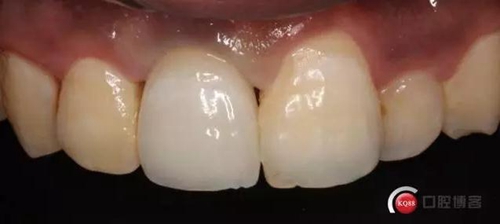

兩月后牙齦恢復(fù)正常穩(wěn)定。正式取模,E.max鑄瓷修復(fù)

可以看出牙齦袖口很漂亮,修復(fù)體外形也不錯(cuò),就是顏色偏白一點(diǎn),讓患者改色,患者覺得已經(jīng)很滿意了,而且考慮其他牙以后做美白,所以不換了。

可以看出修復(fù)體的邊緣密合度都很好。希望這次修復(fù)能夠讓這顆牙多服役幾年吧